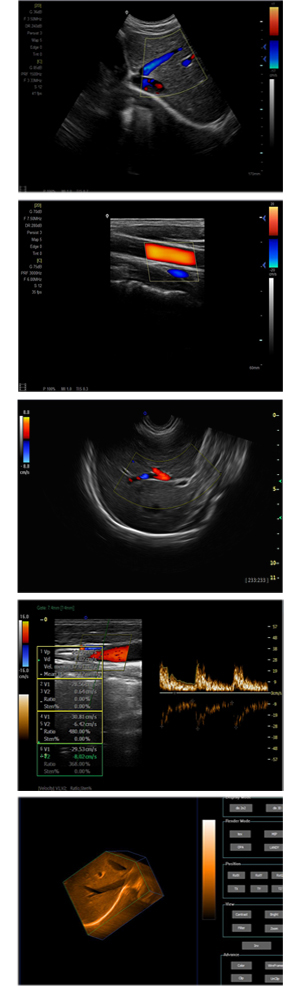

為高集成數(shù)字式彩色多普勒系列產(chǎn)品之一,廣泛實施于腹部,產(chǎn)科,婦科,血管,小器官,泌尿,新生兒和兒科等臨床,屬全身應(yīng)用型彩色多普勒儀器。

●全身應(yīng)用型包含2D/CFM/PDI/PW/ M等掃描模式;

●升級版可選配3D、反向諧波等高級功能。